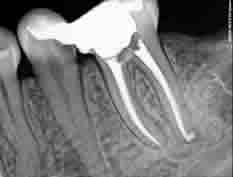

DENTORIUM ordinacije opremljene su sofisticiranim sustavima za tretiranje korijenskog kanala, čišćenje i proširivanje čak i najtanjih kanala koristeći nikal-titan (NiTi) rotirajuće instrumente. Korijenski kanali nerijetko su čitav sustav razgranatih zubnih kanalića koji se šire kao delta rijeke (otuda i ime - root delta). Cijelo to područje treba biti očišćeno i dezinficirano. Neočišćeni ostatak tkiva u kanalu predstavlja područje za razvoj bakterije koje uzrokuju upalu. Zahvaljujući Obtura i Touch'n'Heat toplinsko kondenzacijskim tehnikama punjenja kanala, stomatolozi DENTORIUM ordinacija mogu hermetički ispuniti i najsitnije kanaliće. Zub tretiran na ovakav način služiti će pacijentu mnogo godina, a korijen se može koristiti za buduće složene protetske rekonstrukcije.

DENTORIUM ordinacije opremljene su sofisticiranim sustavima za tretiranje korijenskog kanala, čišćenje i proširivanje čak i najtanjih kanala koristeći nikal-titan (NiTi) rotirajuće instrumente. Korijenski kanali nerijetko su čitav sustav razgranatih zubnih kanalića koji se šire kao delta rijeke (otuda i ime - root delta). Cijelo to područje treba biti očišćeno i dezinficirano. Neočišćeni ostatak tkiva u kanalu predstavlja područje za razvoj bakterije koje uzrokuju upalu. Zahvaljujući Obtura i Touch'n'Heat toplinsko kondenzacijskim tehnikama punjenja kanala, stomatolozi DENTORIUM ordinacija mogu hermetički ispuniti i najsitnije kanaliće. Zub tretiran na ovakav način služiti će pacijentu mnogo godina, a korijen se može koristiti za buduće složene protetske rekonstrukcije.Tretmani korjenskih kanala u našim ordinacijama su bezbolni!